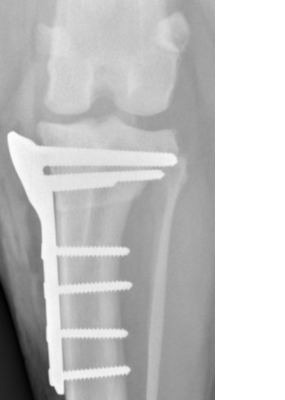

Ostéotomie tibiale (TPLO) : modifie la géométrie du tibia pour que le ligament croisé ne soit plus nécessaire à la stabilité. Le fragment tibial supérieur est pivoté et fixé par plaque et vis. Cette technique offre une récupération plus rapide, des résultats fiables (95 % de succès) et protège le genou opposé. (Voir la fiche santé info TPLO)

L’arthrose déjà présente ne peut être éliminée, mais un traitement précoce limite sa progression

Suivi post-opératoire